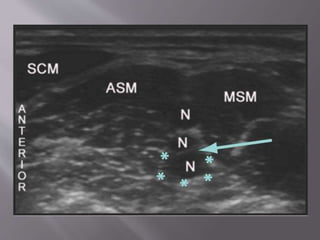

 Basically ultrasound guided superficial cervical

plexus block

 Ensures deeper components of the SCP are

anesthetized

 Position: Supine/Sitting

 Landmarks: Posterior border of the

sternocleidomastoid muscle at the level of the

external jugular vein

 Local: 5-15 mL